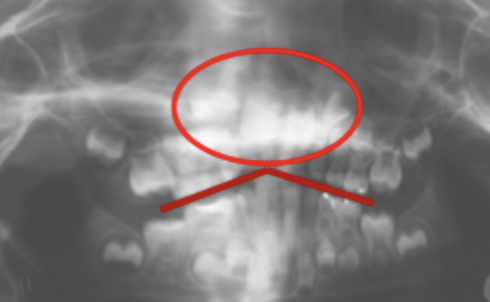

Patient position - Antero-posterior error

Patient too forward, too close to film. Teeth narrowed.

Patient too backwards, too far away from film. Teeth magnified & widened.